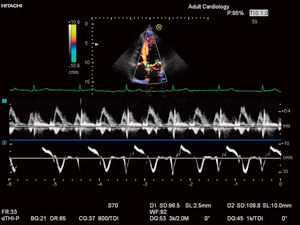

■ Dual Doppler

“Dual Doppler”では,2か所のサンプル点のドプラ信号を同時に検出できる。血流だけでなく,組織ドプラとも組み合わせることができ,僧帽弁通過血流波形の拡張早期波(E)と組織ドプラによる拡張早期僧帽弁輪速度(e')の比であるE/e'などを同一心拍で計測できるようになり,不整脈の症例においても威力を発揮する(図9)。

図9 Dual Doppler